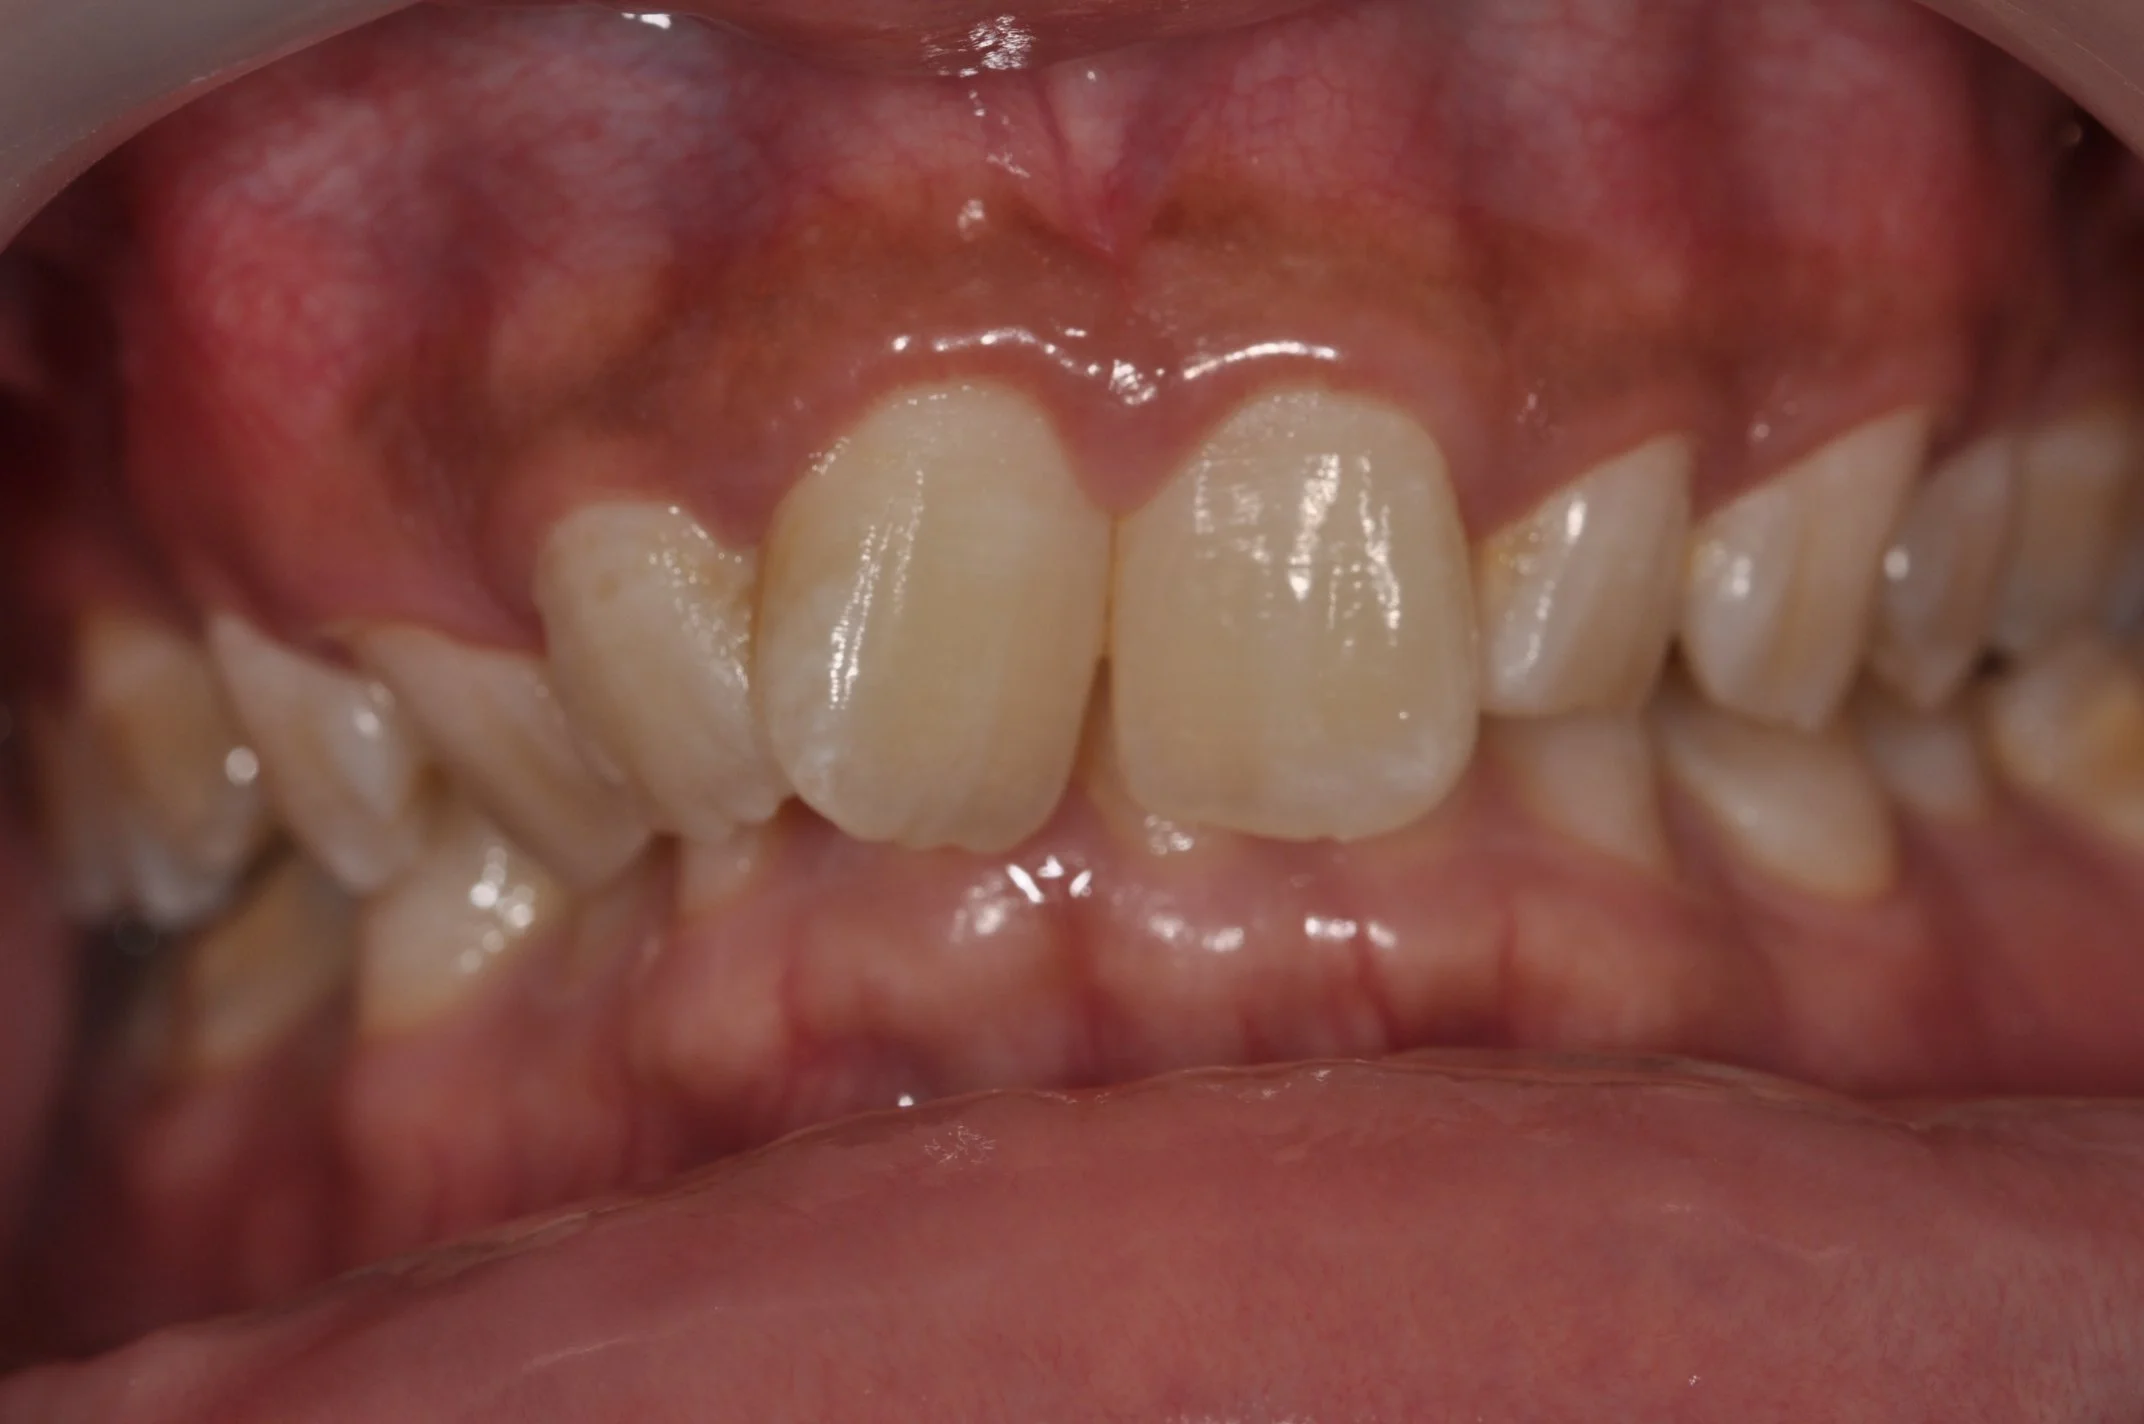

Jason Hp PA Preop.jpg

Failing Natural Central Incisor

(Upper front tooth)